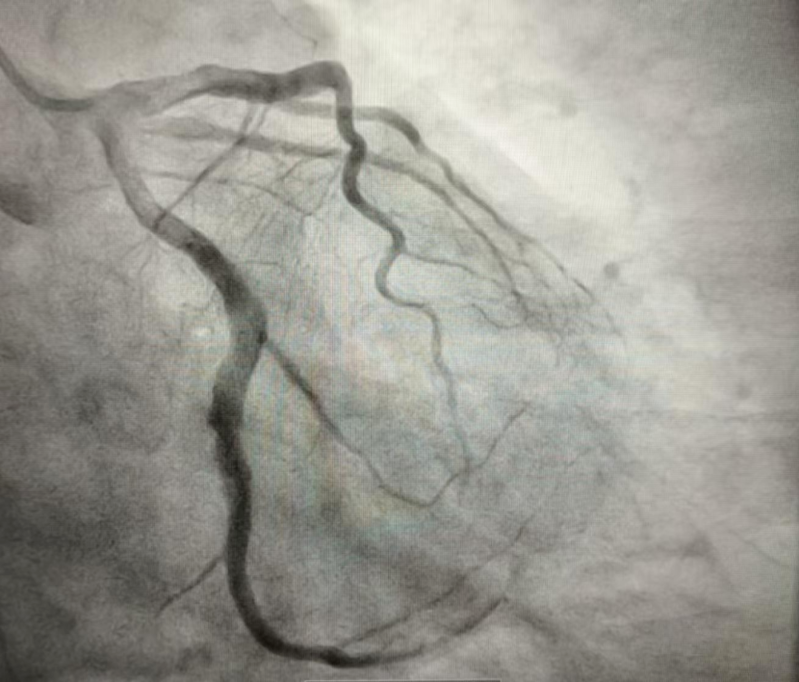

4天后,患者复查冠脉造影示回旋支中段可见可疑夹层征象,前向血流TIMI 3级(图3)。

(图3)